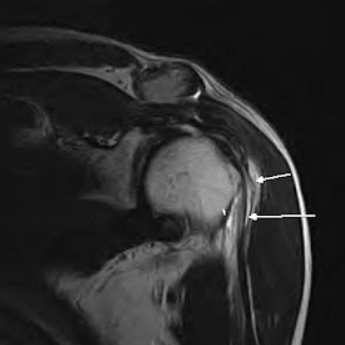

MRI, 초음파 등 영상검사로 힘줄 파열 정도를 평가합니다.